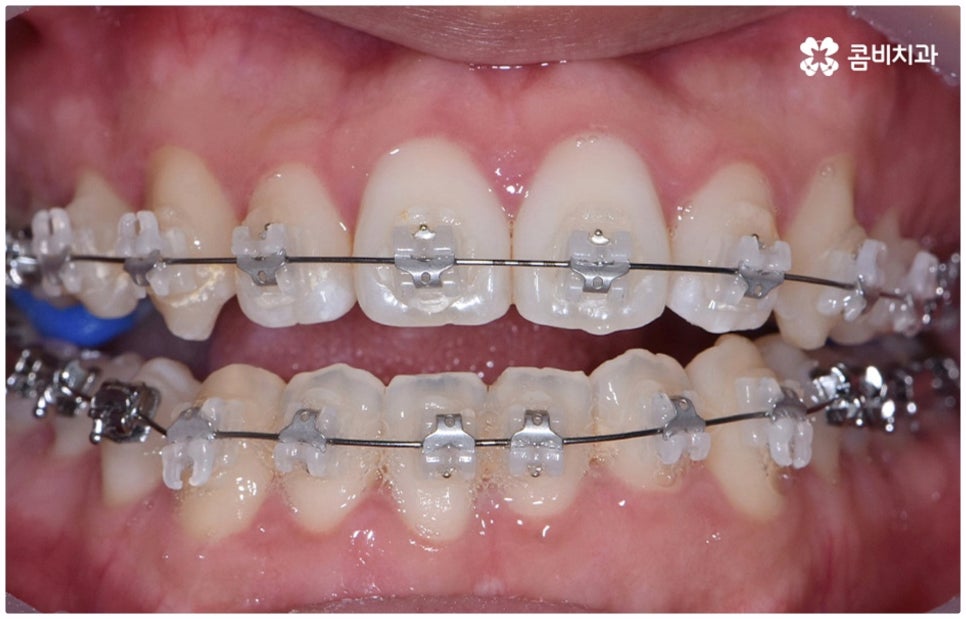

물론 교정 치료에 적기가 정해져 있는 것은 아니기 때문에 성인 이후 중장년 환자분들이라도 교정 치료가 불가능하지는 않으며 상황에 따라 비수술적인 방법으로도 얼마든지 불편함을 줄일 수 있는 경우가 있으니 정확하게 진단한 후 각자에게 맞는 교정 계획을 세워 무리하지 않게 치료를 진행하시길 바라고 있어요. 특히 턱관절과 관련된 부분을 개선하기 위해서는 양악 수술 밖에 방법이 없는 것이 아닌가 생각하셨던 분들이라면 먼저 치과에 내원하셔서 검진과 상담부터 진행해 보시면 마음의 부담을 덜 수 있어 좋을 거예요. 부정교합 3급 치열 (절단교합과 일부 반대교합이 병행되어 있음) 을 가지고 있는 성인분도 교정 치료를 통해 훨씬 자연스럽게 개선이 가능할 수 있으며, 관련 기술 개발 및 미니스크류 등 여러 장치의 발전을 통해 예전에는 적용이 어려웠던 케이스들도 이제는 교정 치료의 도움을 받을 수 있습니다.

치료 계획을 세울 때는 3D CT 같은 정밀 검진 기계를 통해 부정 교합의 정도 및 상하악 관계, 잇몸 건강 상태 등을 꼼꼼하게 살펴보고 회복력과 진행 속도에 영향을 주는 연령, 생활 습관, 평소에 앓고 있는 질환은 없는지 등도 모두 고려하여 세밀한 맞춤 플랜을 세워야 하며 같은 주걱턱 증상이라도 심각한 정도와 턱의 모양에 따라 교정 방법이 달라질 수 있는 만큼 다양한 케이스를 다뤄본 임상 경험을 바탕으로 높은 기술력을 가지고 있는 의료진에게 교정 치료를 받는 것이 굉장히 중요한 포인트라고 할 수 있어요. 정밀 검진 장비 보유 여부, 술자의 뛰어난 숙련도와 함께 체계적인 교정 시스템을 갖추고 사후 관리를 철저하게 해 주는 치과에서 처음부터 끝까지 무리하지 않게 치료를 받는 것도 중요하니 이런 부분도 체크해 보시길 권유드리고 있습니다.

위 사진은 이해를 돕기 위한 이미지이며, 환자의 동의하에 진행되었습니다.

전체 치료 기간은 약 18개월이 소요되었으며,